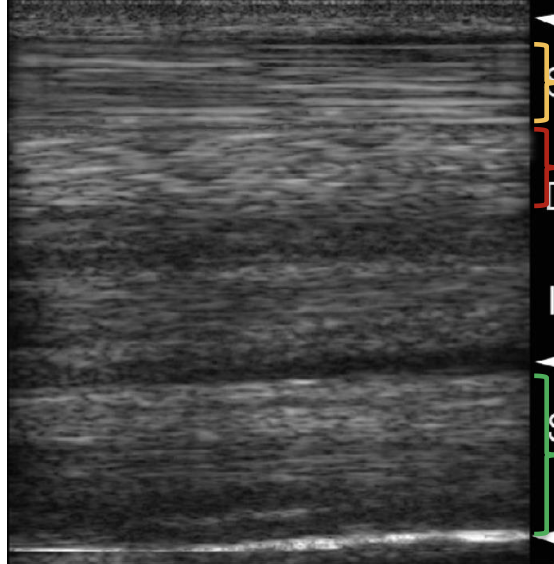

what structure is indicated by the green bracket?

suspensory ligament

what structure is indicated by the red bracket?

DDFT

what structure is indicated by the yellow bracket?

SDFT